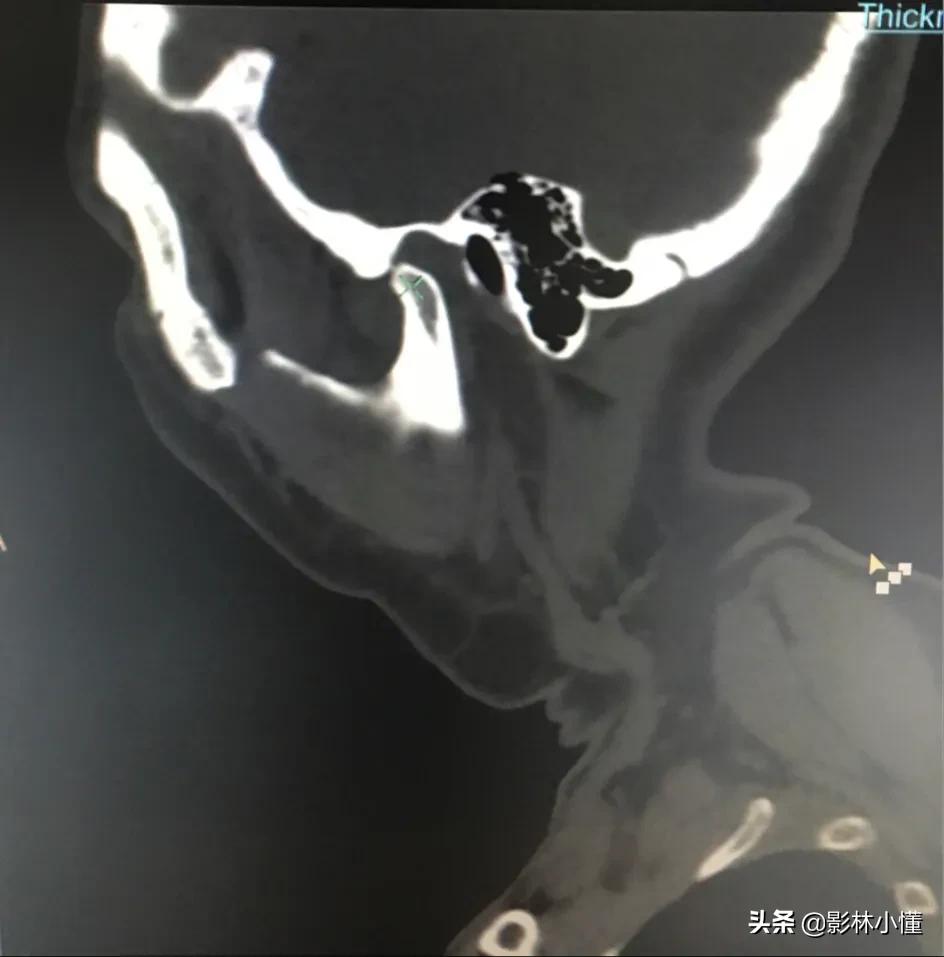

以前颞颌关节常规的检查方法包括X线平片及关节造影。现在已基本不用。颞颌关节CT和MR扫描是目前最常用的方法。颞颌关节检查体位特殊,并且需要做闭口位、张口位。CT可以发现关节骨质的改变,是否有吸收及骨质破坏,关节间隙是否改变、是否张口受限及周围软组织肿胀等情况。(下图显示双侧颞颌关节活动度不一致)